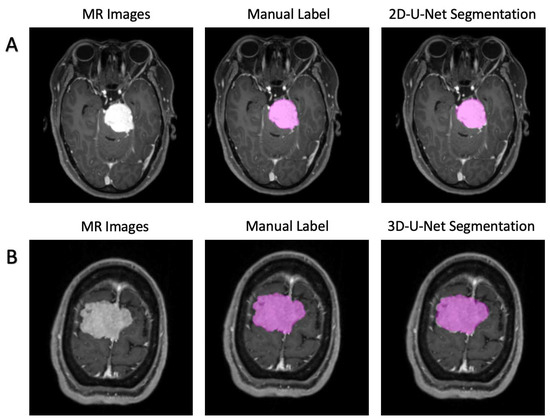

The segment model was designed with a modified U-Net, a convolutional deep neural network (CNN), showing promising ability in segmentation tasks of medical images (Figure 1B) [10]. The inputs could be selected as a 3D stack or a single 2D image depending on the task needs. To compare their performances, we established two models with both 2D-U-net and 3D-U-net, and the parameters were set as follows:

In most cases, both 2D-U-Net and 3D-U-Net can accurately segment tumors on axial images. Figure 2 represents the predicted section examples from the models’ tumor predictions in comparison with the manual segmentations. Specifically, the performances for the 2D-U-net network in the validation groups were: dice = 0.920 ± 0.009, Jaccard = 0.851 ± 0.016, TPR = 0.999 ± 000, FPR = 0.000 ± 0.000, and calculation time = 70 ms/image. Additionally, for 3D-U-net, the results were: dice = 0.873 ± 0.020, Jaccard = 0.774 ± 0.015, TPR = 0.999 ± 0.002, FPR = 0.000 ± 0.000, and calculation time = 390 ms/image. The 3D visualization of our detections and ground-truth segmentations are shown in Figure 3.

Figure 2. Two examples of the segmentation predicted by U-Net. (A). 2D-U-Net architecture; (B). 3D-U-Net architecture.